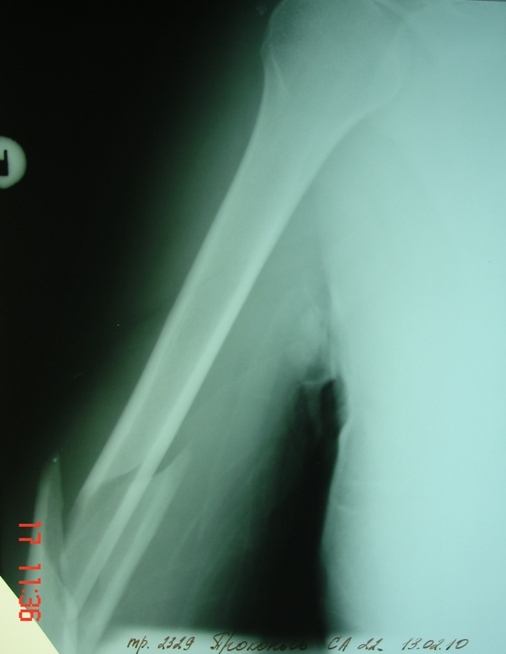

[Ortho] Перелом плеча - тактика лечения

Вчера  поступил этот больной. Перелом закрытый,

неврологии  нет.  Думаем вначале  лечить  консервативно. Снимки в

приложении.

Имя     : Прямой.JPG

Имя     : Боковой.JPG